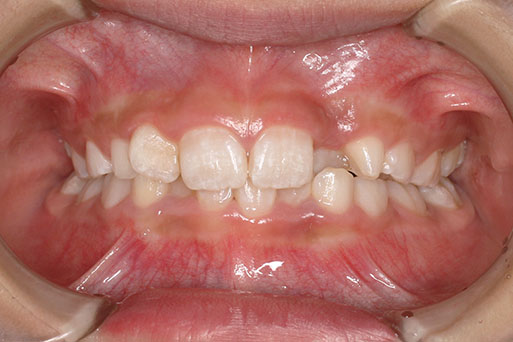

『前歯ががたついて生えてきた』 一般歯科から紹介の患者さんです。 上下4前歯に叢生がみられます。かみ合わせが深く、過蓋咬合。 上顎前歯は舌側傾斜。 永久歯の萌出スペースが上下とも5mmほど足りませんし、 おそらく、これから生えてくる犬歯は八重歯になる状況です。 治療方針としては、小児矯正で叢生(がたつき)を減らし、 永久歯列が生えてから、中学生ごろから本格矯正(マルチブラケット装置)を行います。 十分に側方拡大でスペースを確保し、更に、まだ生えていない永久歯の位置と方向が良ければ、きれいに生えそろうことにより、本格矯正での治療が必要ない場合もありますが頻度的には少ないです。 ある程度はきれいに生えてきても、左右の歯の高さの違いや、歯の回転、角度のズレが残る場合が多いからです。 その多少のがたつきが気にならないのでしたら、小児矯正で終了です。